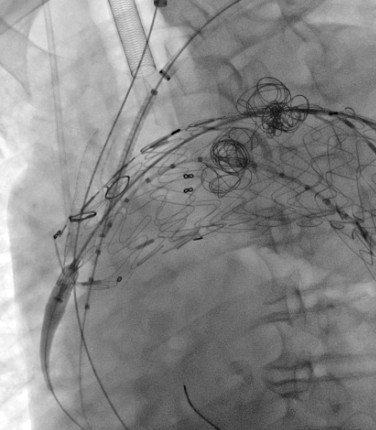

(體外開窗)TEVAR手術(shù)緊張有序進(jìn)行中

穿刺股動(dòng)脈、切開頸動(dòng)脈、肱動(dòng)脈建立入路,超選內(nèi)漏口、栓塞瘤腔,體外預(yù)開窗、重建弓上動(dòng)脈......血管外科兩組人馬同時(shí)開工,有條不紊。在麻醉科林芩主任團(tuán)隊(duì)的密切配合下,一系列步驟緊張有序地進(jìn)行著。手術(shù)持續(xù)了4個(gè)多小時(shí),當(dāng)最終的造影確認(rèn)內(nèi)漏完全封閉、假性動(dòng)脈瘤成功隔絕,并且主動(dòng)脈弓上的重要分支動(dòng)脈血供良好的那一刻,血管外科團(tuán)隊(duì)成員都已忘卻了身上幾十斤的鉛衣和滿身的汗水。夏印主任和黎成金主任不禁對(duì)視一笑:“拆雷成功,又救了一條命?!?

彈簧圈栓塞瘤腔

左頸總動(dòng)脈、鎖骨下動(dòng)脈雙開窗

瘤腔及內(nèi)漏成功封堵,弓上分支動(dòng)脈血流通暢